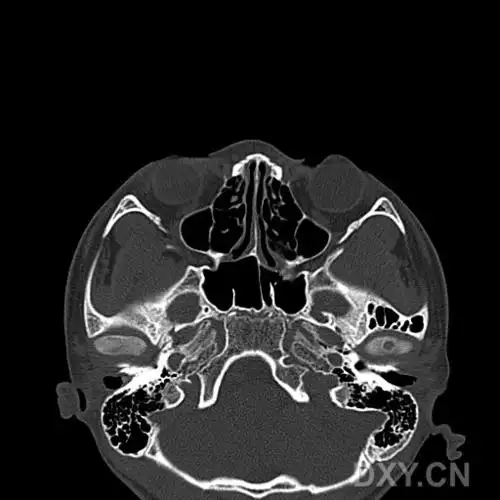

鼻骨骨折影像学诊断

鼻及鼻窦影像解剖及相关疾病影像诊断